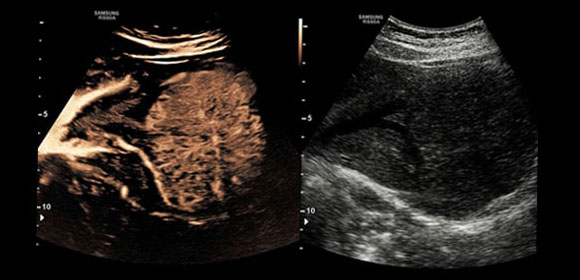

Tehnologia CEUS + profită de proprietățile excelente ale mediilor de contrast cu ultrasunete. Atunci când sunt stimulate de presiunea acustică scăzută, microbulele gazoase reflectă atât frecvențele de bază, cât și semnalele armonice.

S-Shearwave